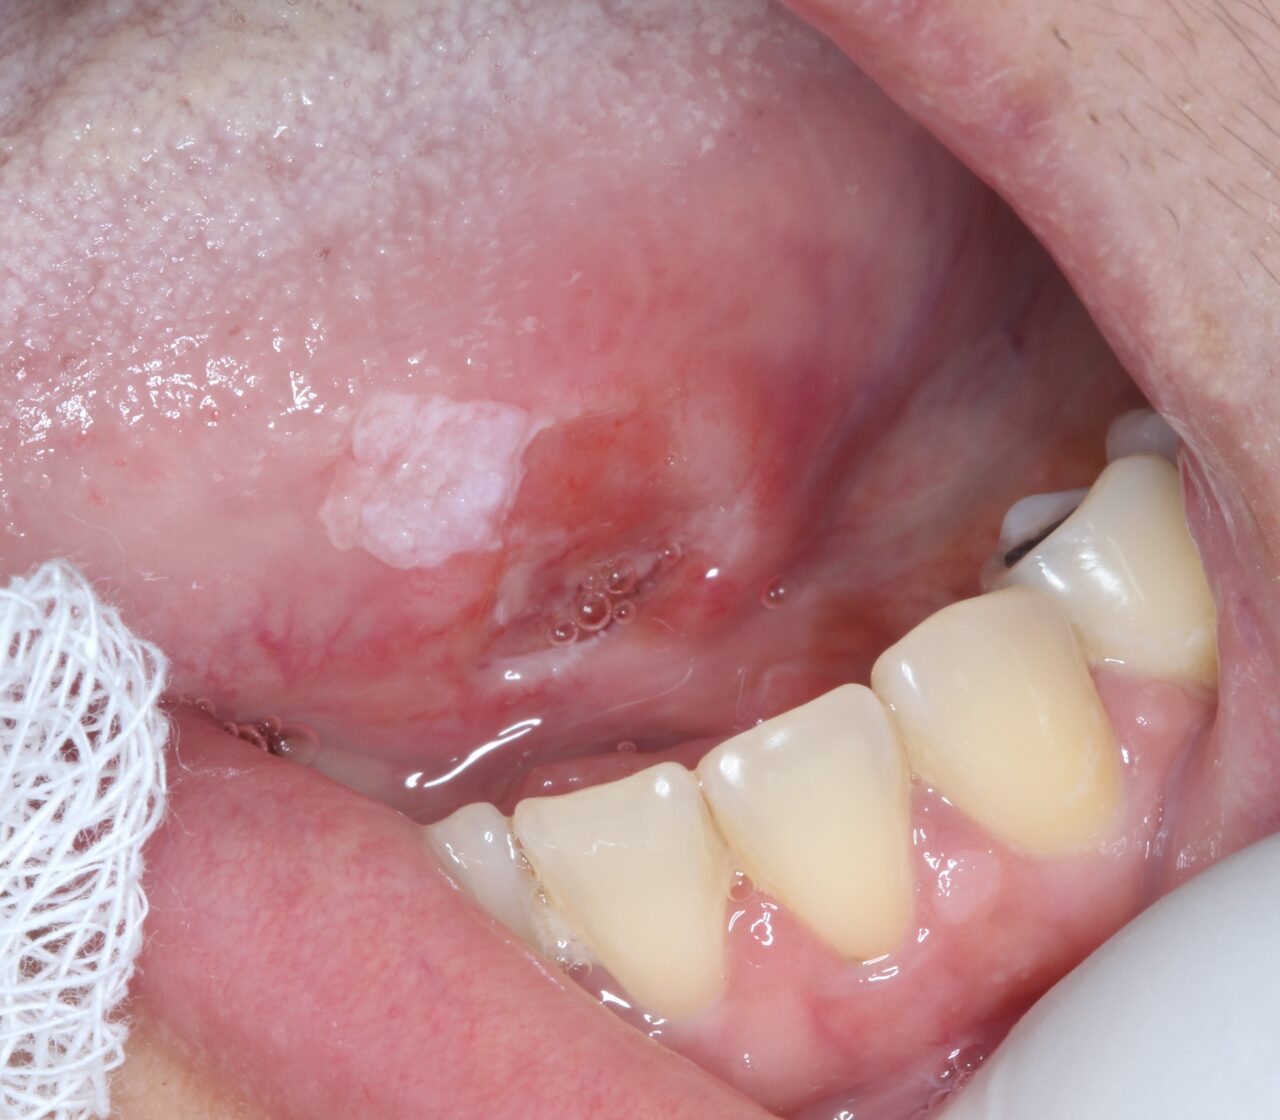

O câncer de boca pode começar de forma silenciosa, com pequenas alterações na mucosa que muitas vezes não doem. Lesões que não cicatrizam em até 2 ou 3 semanas, manchas brancas ou vermelhas persistentes e nódulos endurecidos são sinais de alerta. O diagnóstico precoce é um dos principais fatores para aumentar as chances de tratamento […]